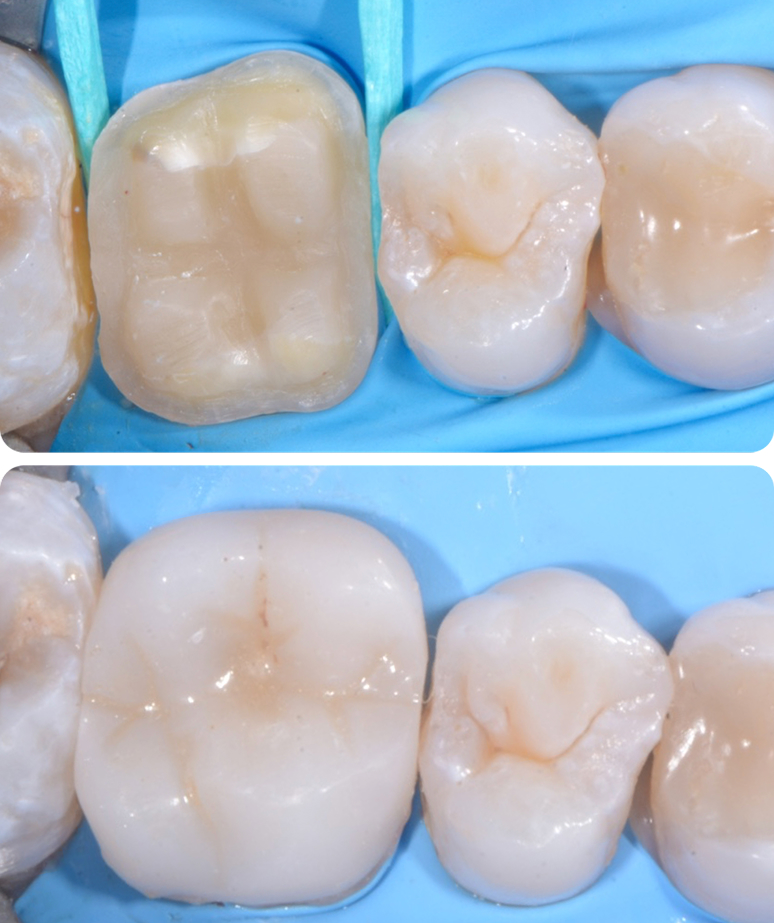

Oggi, l’odontoiatria conservativa comprende anche restauri complessi, in grado di ricostruire fino al 90% della struttura dentale compromessa. Con gli sviluppi delle tecniche e dei materiali, stiamo progressivamente riducendo l’uso delle corone protesiche, sostituendole con soluzioni più conservatrici, come ad esempio gli intarsi. Questi approcci, meno invasivi, offrono vantaggi sia estetici che funzionali, garantendo nel tempo risultati più duraturi e naturali.

L’utilizzo di intarsi rappresenta un esempio di odontoiatria di eccellenza, dove l’attenzione alla preservazione del dente naturale e la ricerca di soluzioni altamente performanti sono al centro di ogni trattamento. Queste tecniche, grazie alla loro precisione e alla qualità dei materiali, permettono di ottenere risultati estetici superiori, mantenendo nel contempo una durata e una resistenza ottimali.